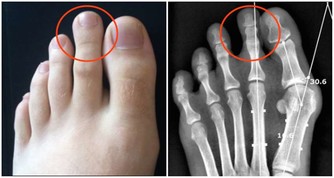

1、怕老:隨著年齡的增長,人體軟骨營養缺乏,骨骼中的無機物增多,骨骼彈力與韌性減低,易導致關節軟骨和骨退行性病變。

2、怕胖:體重增加,下肢關節承重的壓力也會增加,引起體位、步態變化,改變關節的生物力學,發生膝內翻或膝外翻,也就是常說的“O”形腿或“X”形腿。